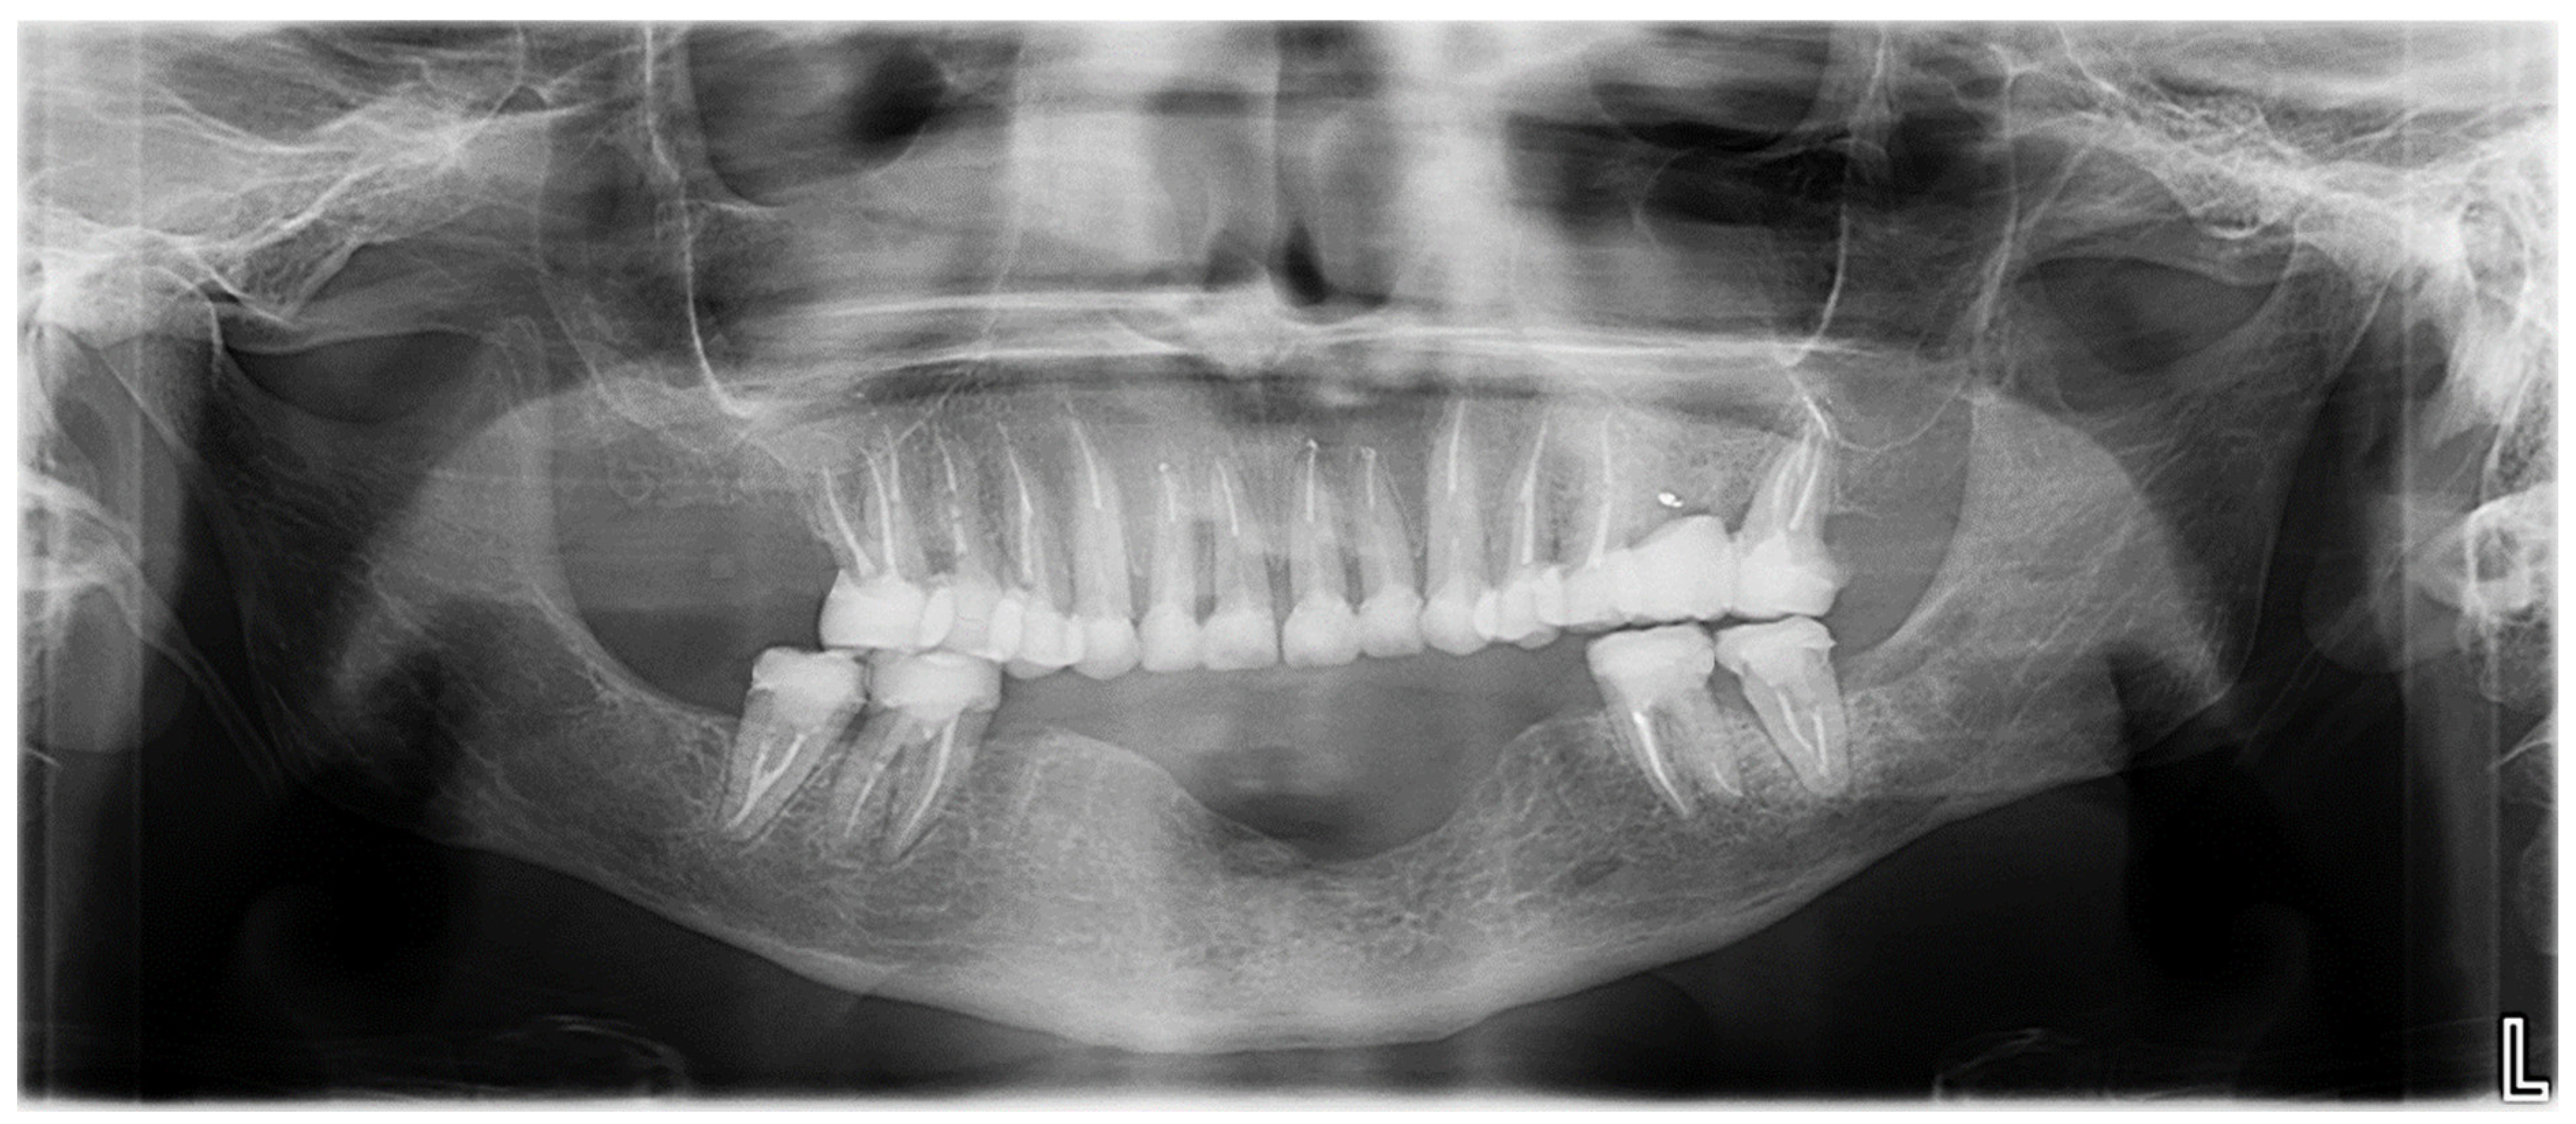

2.2. Clinical History and Diagnostic Assessment

- First GA session (March 2023, lasted 3 h and 30 min): Pre-prosthetic care for mandibular teeth.

- Second GA session (June 2023, lasted 3 h and 30 min): Pre-prosthetic care for maxillary posterior teeth, and non-traumatic extractions of teeth 17 and 26.

- Third GA session (June 2023, lasted 2 h and 30 min): Pre-prosthetic care for maxillary anterior teeth [9].